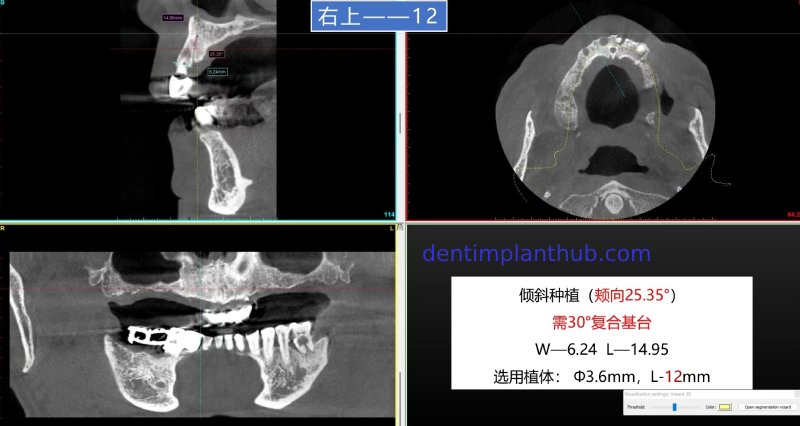

The specific conditions of each tooth position and the implant plan

For tooth 12, with a width of 6.24 and a height of 14.95, an implant with a diameter of 3.6 and a length of 12 is selected. It needs to be implanted at an inclination. The buccal angle is 25.35°, and a 30° composite abutment is required.